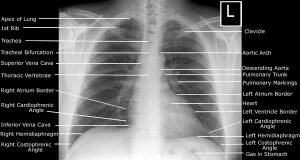

The procedure works through radiation, the ray pass through the body and most other objects as well. The ribs and the spine will absorb the maximum amount of radiation and will look white, and tissues and muscles appear black. If there is any discrepancy it will show in the image otherwise the image will remain clean.

The interpretation will be done by a certified radiologist. The images will be analyzed by him or her and a report will be thus created. All the radiologists involved with the CIC medical exam panel are efficient and well trained so you can be sure of getting the right results. After you receive the report you must go to your physician and discuss it.